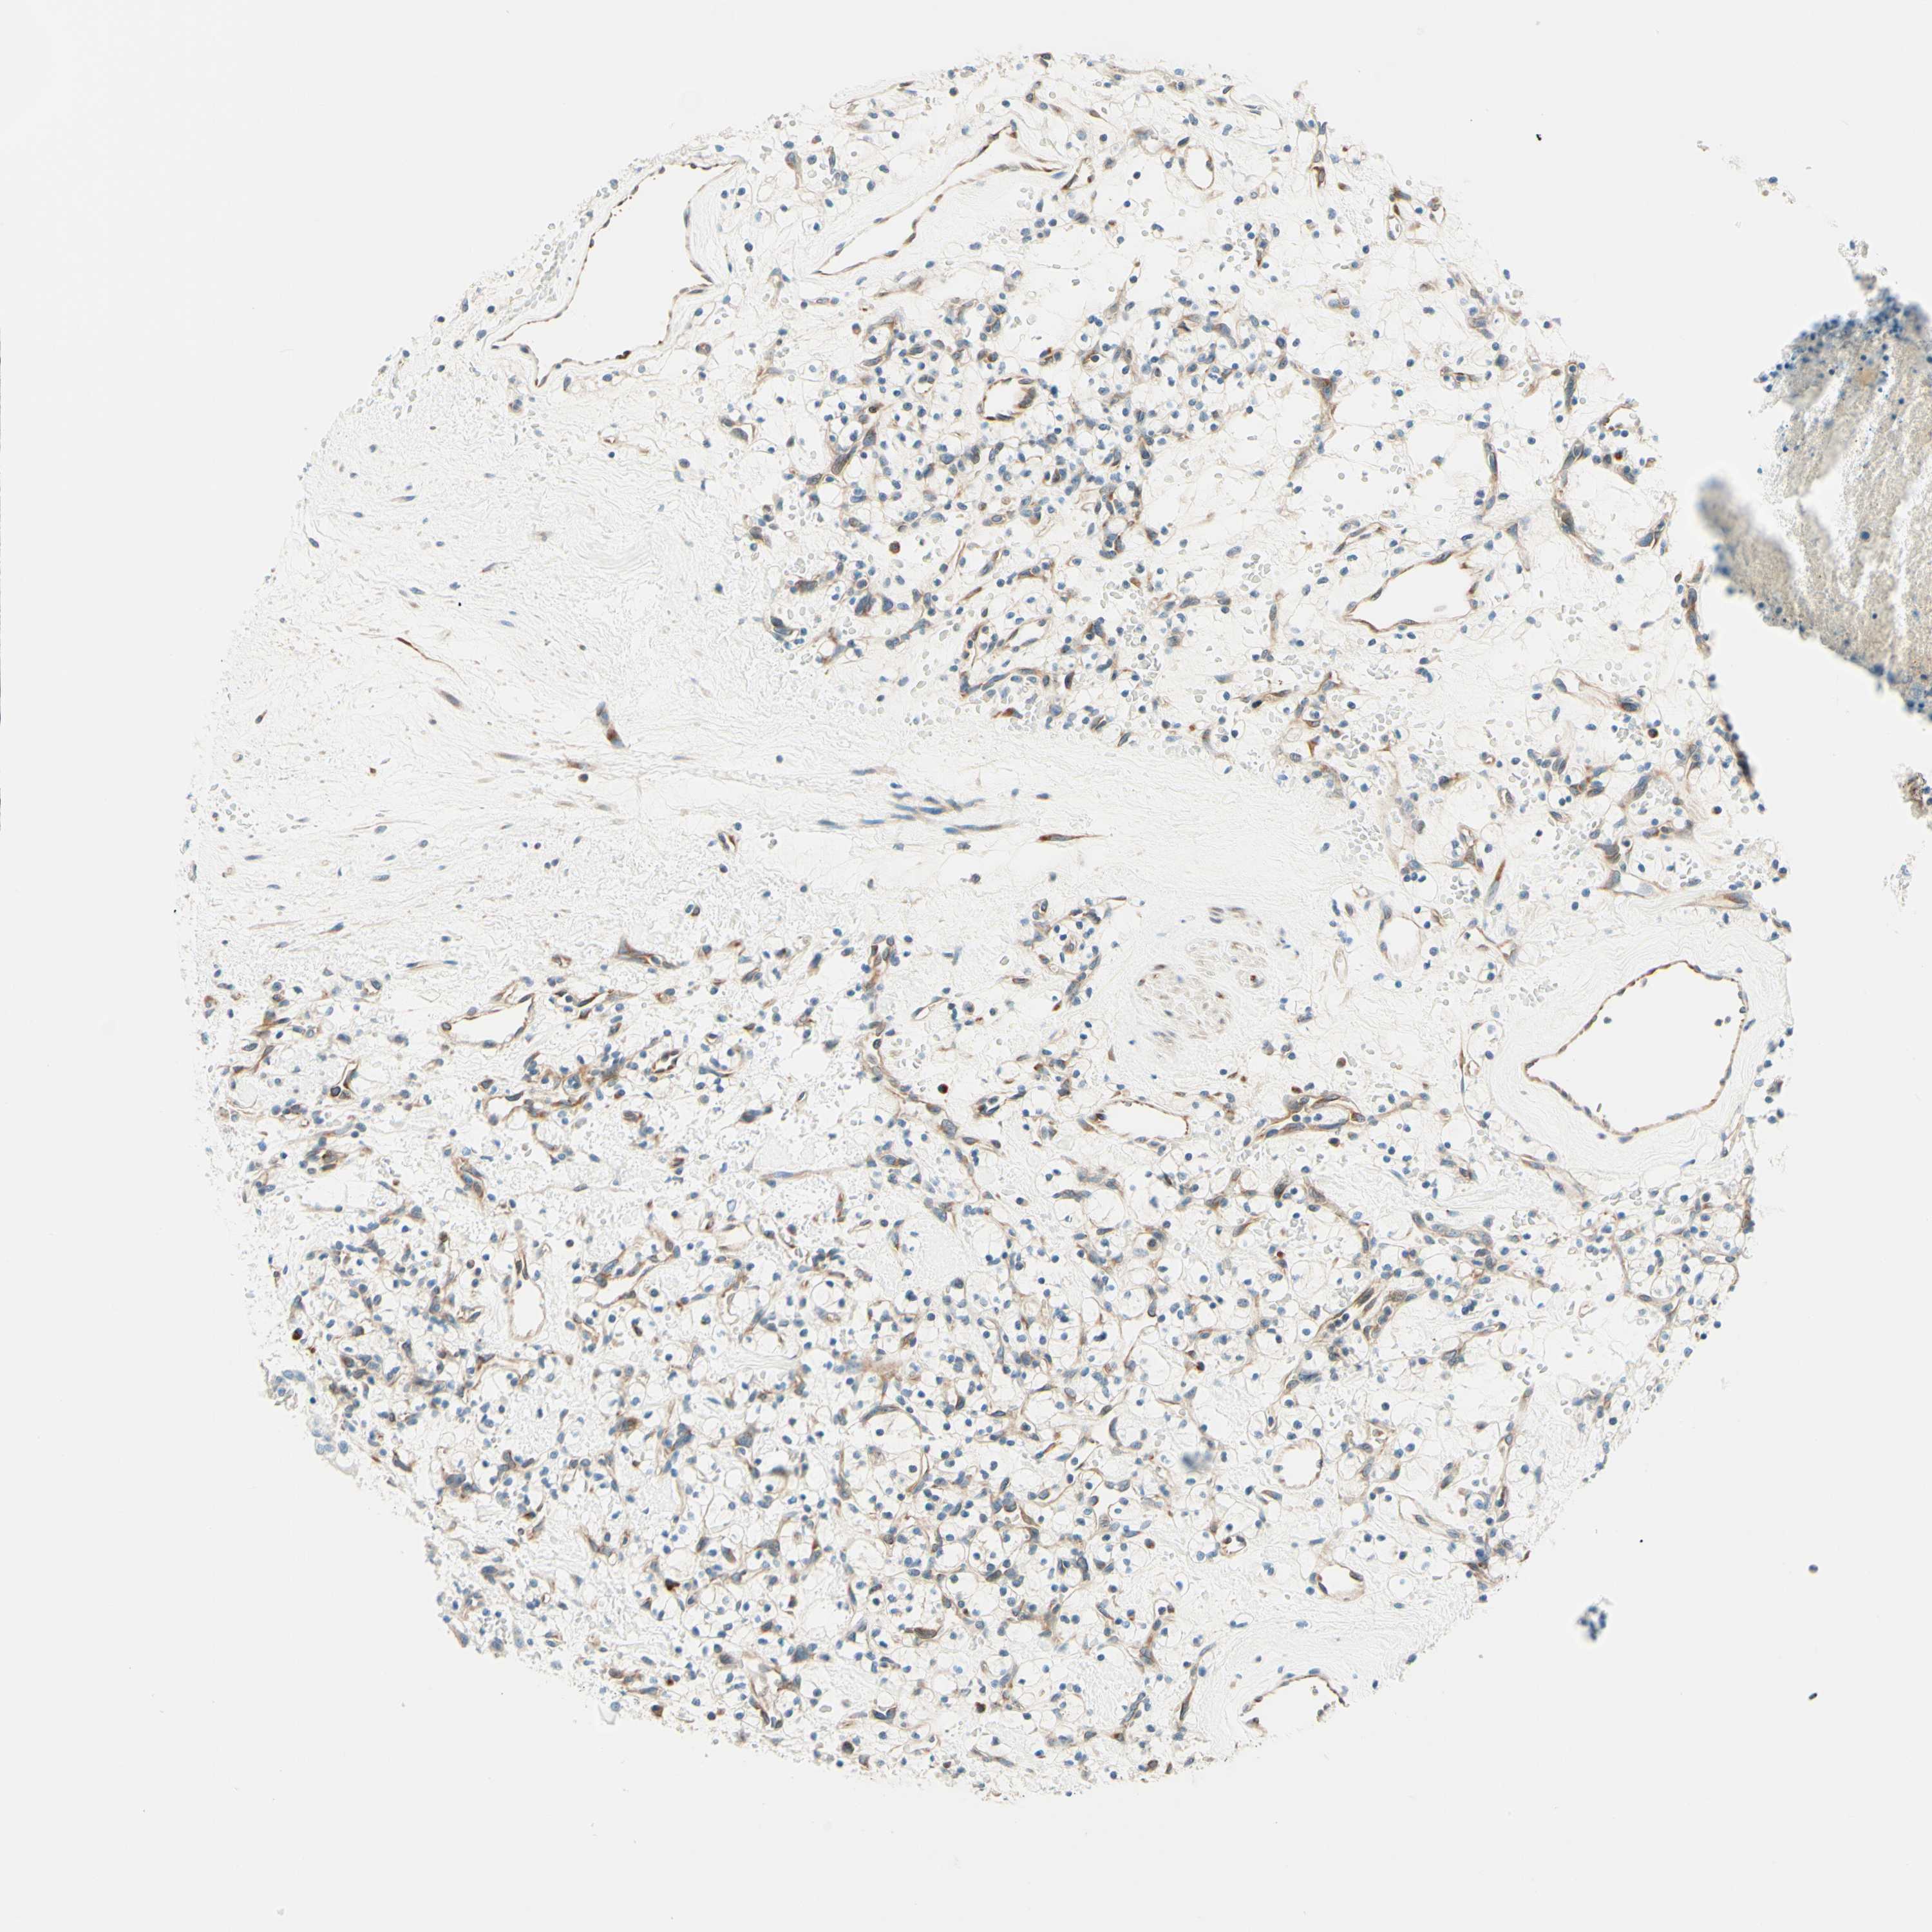

KIDNEY RENAL CLEAR CELL CARCINOMA (VALIDATION) - Interactive survival scatter ploti

The Survival Scatter plot shows the clinical status (i.e. dead or alive) for all individuals in the patient cohort, based on the same data that underlies the corresponding Kaplan-Meier plots. Patients that are alive at last time for follow-up are shown in blue and patients who have died during the study are shown in red.

The x-axis shows the expression levels (FPKM) of the investigated gene in the tumor tissue at the time of diagnosis. The y-axis shows the follow-up time after diagnosis (years). Both axes are complimented with kernel density curves demonstrating the data density over the axes. The top density plot shows the expression levels (FPKM) distribution among dead (red) and alive patients (blue). The right density plot shows the data density of the survived years of dead patients with high and low expression levels respectively, stratified using the cutoff indicated by the vertical dashed line through the Survival Scatter plot. This cutoff is automatically defined based on the FPKM cutoff that minimizes the p-score. The cutoff can be changed by dragging the vertical line or by entering a cutoff value in the square labeled "Current cut-off".

Under the Survival Scatter plot the p-score landscape (black curve; left axis) is shown together with dead median separation (red curve; right axis). Dead median separation is the difference in median mRNA expression between patients who have died with high and low expression, respectively. It is calculated as follows: median FPKM expression of dead patients with high expression - median FPKM expression of dead patients with low expression. This is intended to aid the user in visually exploring custom cutoffs and the associated p-scores and dead median separation.

Individual patient data is displayed and can be filtered by clicking on one or more of the category buttons on the top of the page. Categories describing expression level and patient information include: high, low, alive, dead, female, male and tumor stages. The scale of the x-axis can be toggled between linear and log-scale by clicking on the "x log" button. Mouse-over function shows TCGA ID, patient information and mRNA expression (FPKM) for each patient.

& Survival analysisi

Kaplan-Meier plots summarize results from analysis of correlation between mRNA expression level and patient survival. Patients were divided based on level of expression into one of the two groups "low" (under cut off) or "high" (over cut off). X-axis shows time for survival (years) and y-axis shows the probability of survival, where 1.0 corresponds to 100 percent.

TAOK2 is not prognostic in Kidney Renal Clear Cell Carcinoma (validation)

: 28.82

TCGA RNA samplesi

RNA-seq data is reported as average FPKM (number Fragments Per Kilobase of exon per Million reads), generated by the The Cancer Genome Atlas (TCGA) .

Normal distribution across the dataset is visualized with box plots, shown as median and 25th and 75th percentiles. Points are displayed as outliers if they are above or below 1.5 times the interquartile range. FPKM values of the individual samples are presented next to the box plot.

Average pTPM 30.4

Number of samples 100